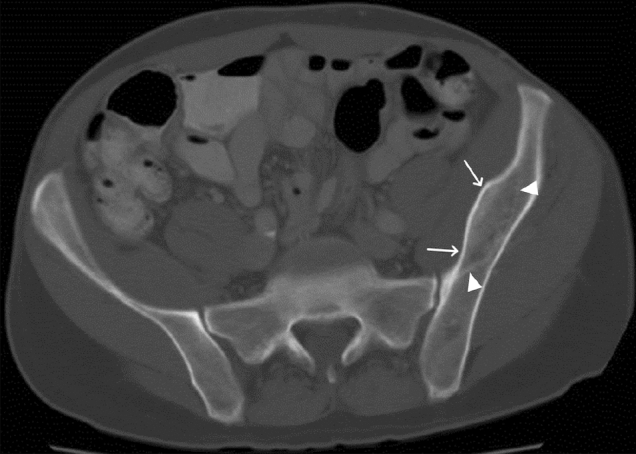

Fig. 1.

43-year-old male with bilateral pectineal muscle myonecrosis. Axial (a) and coronal (b) CT images of the abdomen and pelvis demonstrate ill-defined muscle enlargement and decreased attenuation of bilateral anteromedial compartments of the upper thighs (arrows). Axial (c) and coronal (d) T1W fat-saturated post-contrast MR images demonstrate bilateral peripheral enhancement (arrowheads) of the pectineus muscles surrounding central non-enhancing (arrows) muscle fibers representing myonecrosis